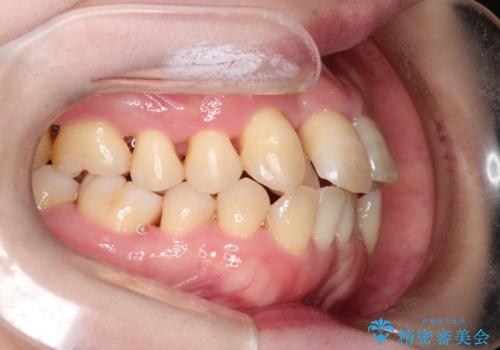

【インビザライン】ずれた前歯の噛み合わせをなおしたい

- 前歯の噛み合わせが悪いことを主訴に来院されました。

歯周病も併発していたため、歯牙への負担が少なくなるように治療計画をたて、インビザラインにて治療を完了しました。

矯正開始前に半年間、歯周治療を行ってからインビザラインを装着しています。